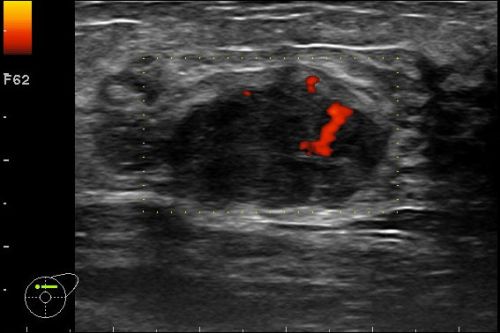

Beurteilungskriterien 2 (Farbdoppler), Problemfälle, Interventionelle Diagnostik, Lymphknoten, Mammographie & Mamma-MRT, S3-Leitlinie Mamma-Ca-Früherkennung, anwendungsbezogene Ultraschallthemen, ausreichend Zeit für Diskussionen, praktische Übungen, Fallbeispiele aus der Praxis, Kasuistiken, u.a.